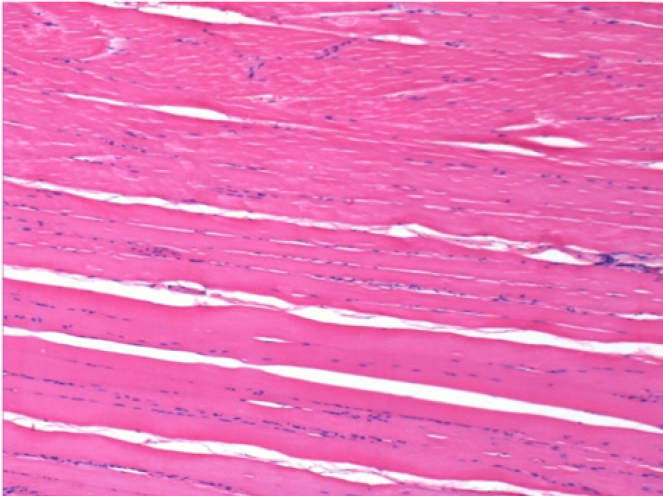

7 meses (D210) después de la inyección IM de Endopeel 0,1 ml en el músculo pretibial derecho.

Restitutio ad integrum (restauración a la condición original) completa después de 7 meses

L :Control 50xD210

R50X-D210